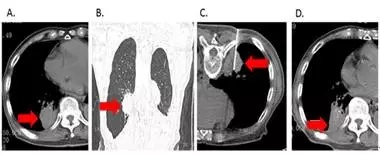

5.RFA还可以用来姑息性治疗缓解晚期肺癌患者的各种不适症状。(图6)

图6:1例88岁高龄肺癌患者术后复发伴肺内及胸膜转移(图A、B所示),重度疼痛难以入睡。患者经肺肿瘤RFA治疗后疼痛明显缓解,睡眠质量明显改善。一年后随访,患者一般状况良好,肺内肿瘤病灶稳定。